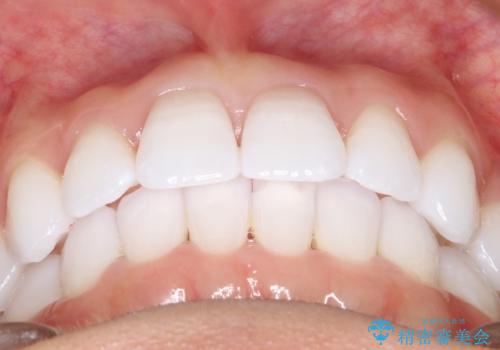

- 前歯の傾きと、ガタガタが気になるとのことで来院されました。

アスリートの方でしたので、競技に支障が少ないインビザラインで治療することとなりました。

前歯の傾きや高さをシミュレーションで患者様と確認しながら、歯並びを仕上げていきました。